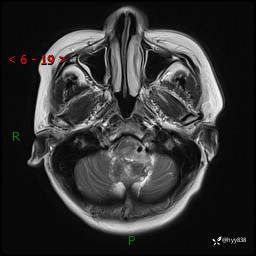

病例中年女性,头晕1年余。看看什么是软,什么是见缝钻---结果公布~

性别:女

年龄:47岁

简要病史:头晕1年余,间断恶心不伴呕吐

颅脑MRI平扫+DWI